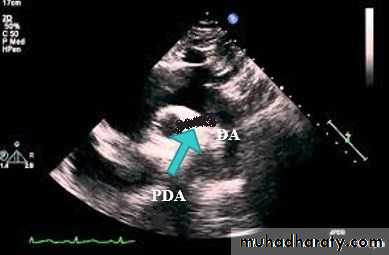

Echocardiography show the PDA and the cardiac chambers.